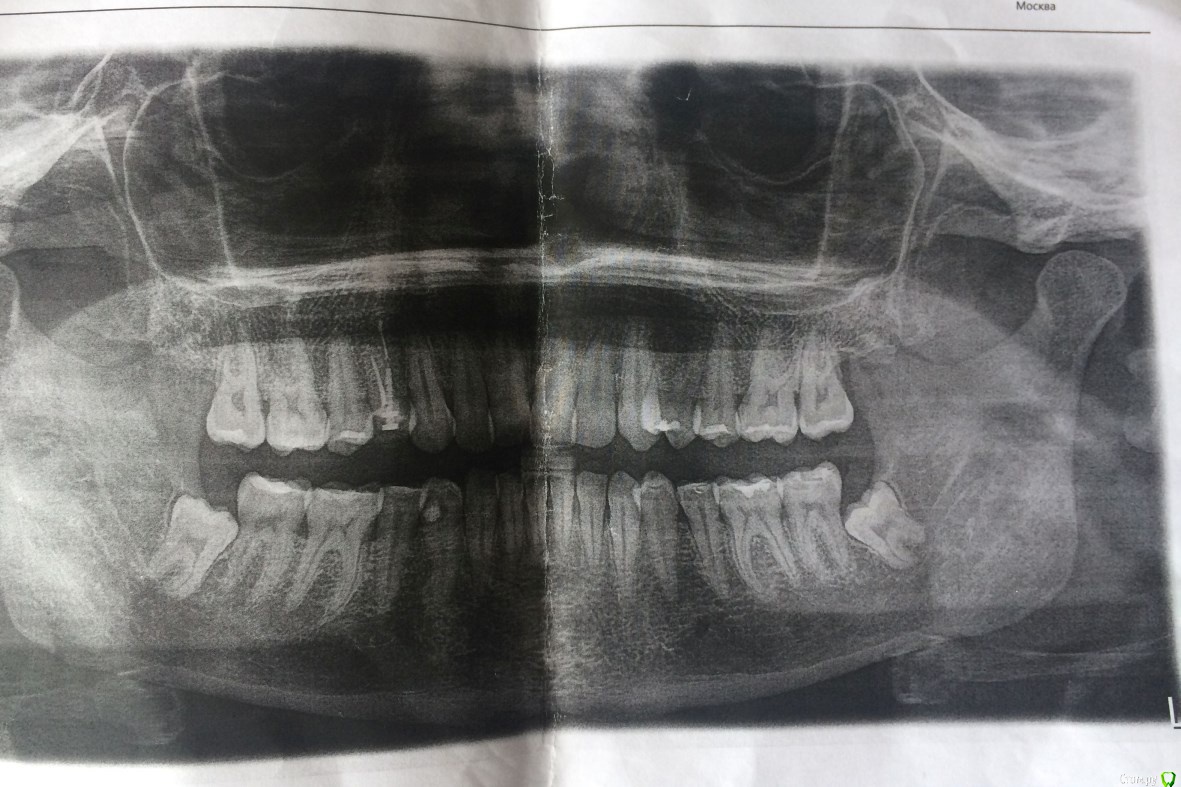

1. Московская клиника, врач работала с ассистентом, оборудование в клинике есть. Сделали контрольный снимок после – прилагаю к теме.

Фото ОПТГ до и после удаления прилагаю.

(Есть также файл КТ до удаления, но я хз, что из него надо брать, так что заскринила, что смогла).

post-60858-0-92958200-1596146772_thumb.jpg

post-60858-0-24490800-1596146821_thumb.jpg

post-60858-0-95972000-1596146826_thumb.jpg

Все выглядит по снимкам и Вашему описанию нормально